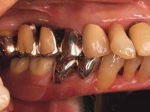

両側5歯症例

両側5歯症例両側5歯症例両側5歯症例 主訴-義歯のバネが壊れて手前の歯が痛んできた。 術前(旧義歯装着、鏡像) 術前(下顎粘膜面、鏡像)術前(下顎粘膜面、鏡像)術前(下顎粘膜面、鏡像) 術前レントゲン術前レントゲン術前レントゲン 術前口腔内(正面観)術前口腔内(正面観)術前口腔内(正面観)